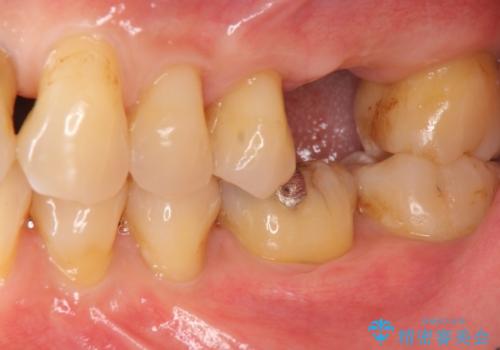

- 歯が割れてしまい、抜歯後のインプラント治療を希望され相談来院されました。

歯が割れるほどの咬合力が強い方でしたので、3本の歯を2本で支えるブリッジではなく、咬合負担能力の増えるインプラント治療にメリットが大きいと言えます。